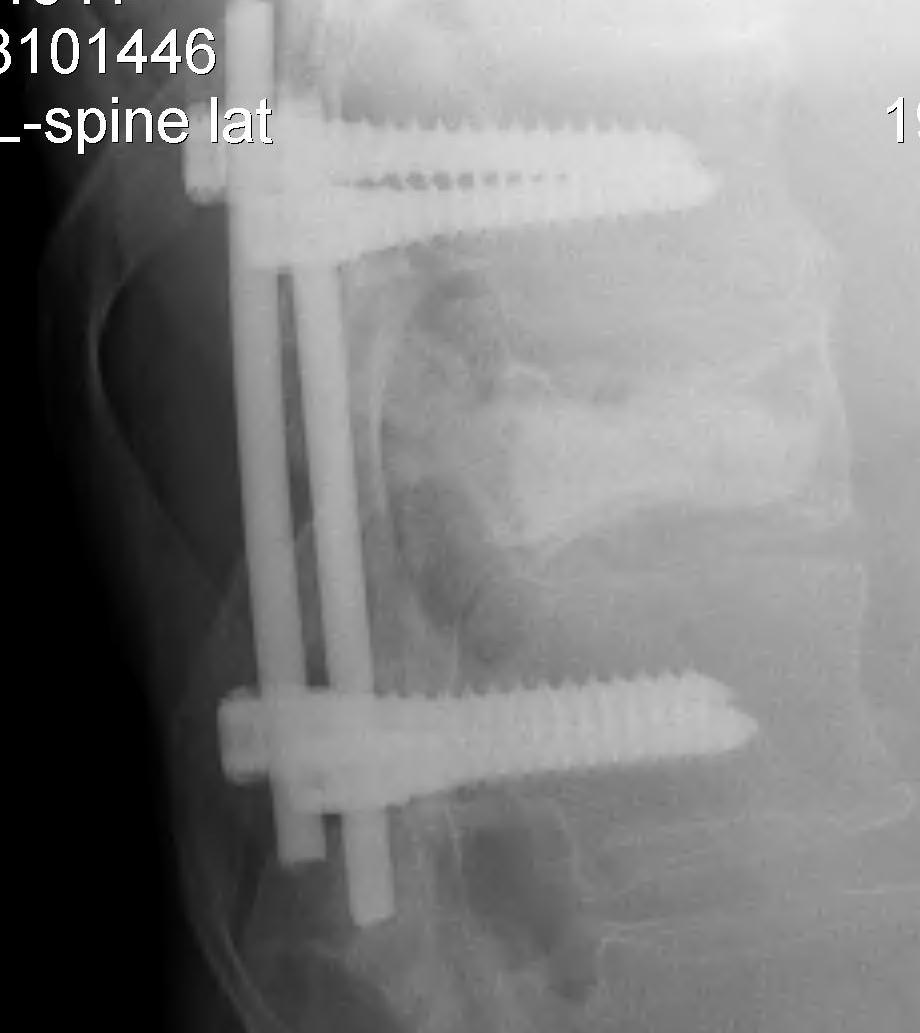

3. Posterior stabilisation

A. Long segment stabilisation

B. Short segment stabilisation + PMMA

3. Corpectomy / PMMA / Anterior stabilisation

Technique

- remove body and disc to dura

- PMMA sufficient if LE < 6 months

- titanium cage and BG / structural graft if LE > 6/12

- stabilised with anterior plates